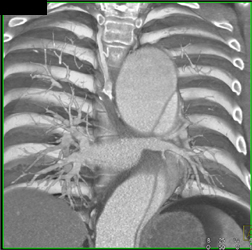

Type A Dissection